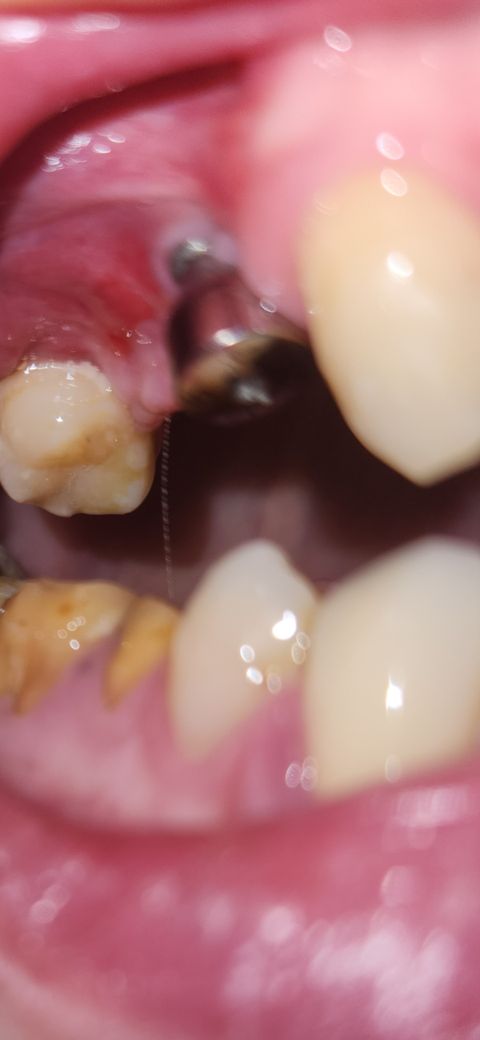

처음에는 구내염인가 싶어 지켜봤는데 잇몸에 구멍과 더불어 8월14일부터 양치질을 쎄게 한건지 빨간게 생겨서 이렇게 여쭈어봅니다.

임플란트 주변에도 경미한 염증이 보이는듯해 보여요.